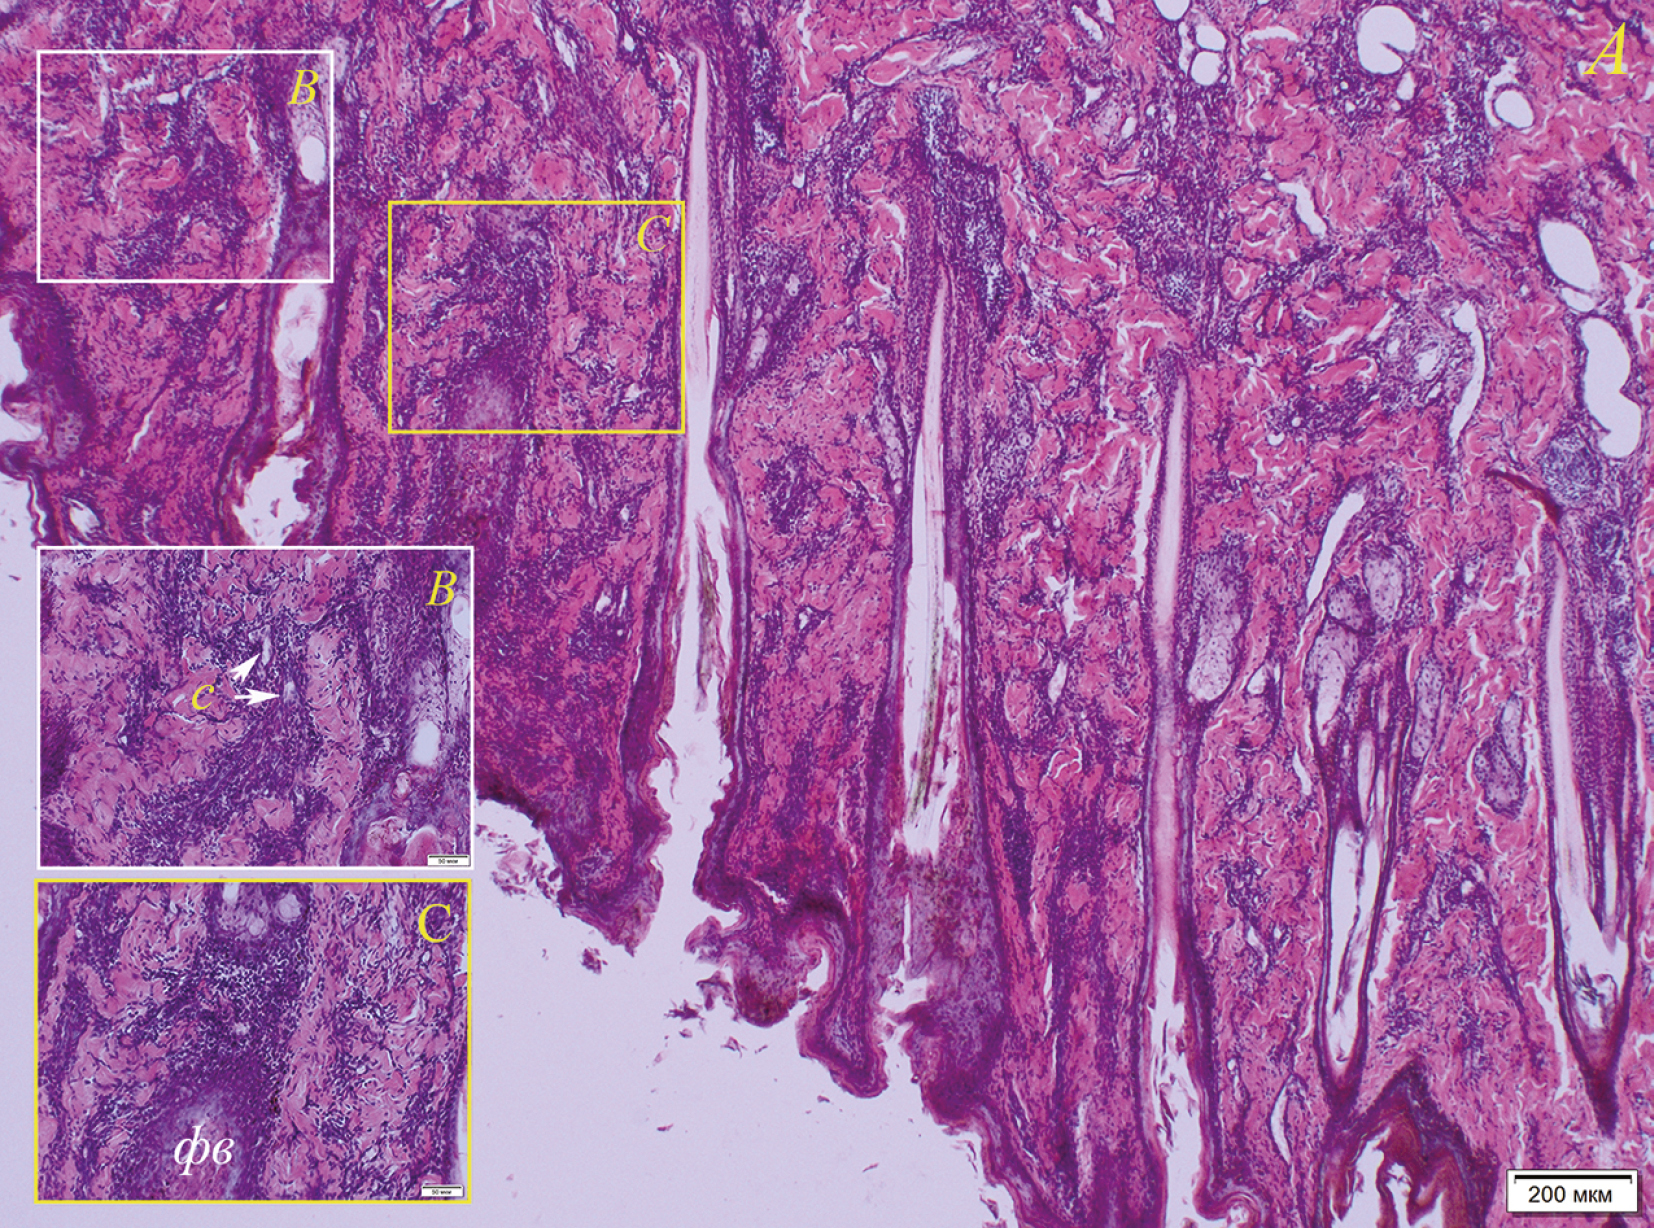

Одновременно с процессом койлоцитоза в субэпидермальных слоях кожи имеются очаги воспаления, локализующиеся в основном периваскулярно и частично перифолликулярно (рис. 11). В более глубоких слоях воспаление усиливается, локализуясь, в том числе, и вокруг потовых желез. Воспалительный инфильтрат представлен лимфоцитами с небольшим количеством гистиоцитов. В срезах кожи с поражениями также обнаружен экзоцитоз, связанный с тем, что лимфоциты мигрируют в волосяные фолликулы (рис. 12). Клетки влагалища волосяного фолликула отечны, присутствуют явления спонгиоза. Описанный комплекс патологических изменений кожи встречался наиболее часто при исследовании пораженных участков у байкальской нерпы.

Рис. 11. Воспаление в дерме кожи ласт байкальской нерпы (№ 5, самка, 2+) (A) с участками периваскулярного (B) и перифолликулярного (C) скопления инфильтрата (лимфоциты с примесью гистиоцитов): с – сосуды (указаны стрелкой), фв – волосяной фолликул. Окраска гематоксилином с эозином.

Рис. 12. Миграция лимфоцитов в волосяной фолликул (экзоцитоз) и спонгиоз эпителиоцитов эпителия волосяного влагалища (№ 1, самка, 2+): фв – волосяной фолликул, л – лимфоциты, мигрирующие в фолликул (указаны стрелками). В выделенных желтым цветом областях показаны эпителиоциты с признаками спонгиоза (отечные эпителиоциты, отделенные друг от друга). Окраска гематоксилином с эозином.